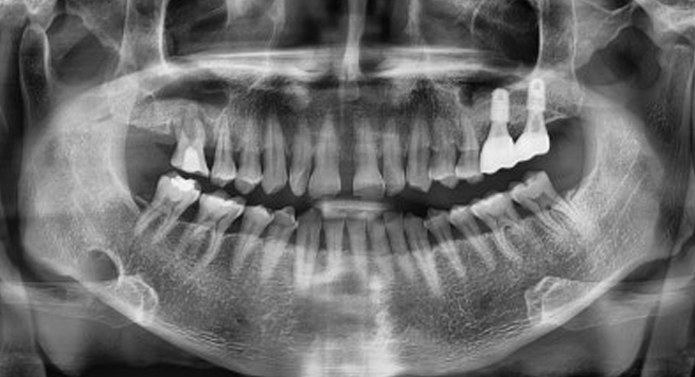

뼈가 부족한 경우에도 가능한 임플란트 솔루션 임플란트를 식립하려면 일정량 이상의 턱뼈가 필요합니다. 하지만 골다공증, 치주질환, 발치 후 방치 등으로 뼈가 부족하거나 얇아져 있는 경우엔 뼈이식이 필요합니다.

환자 개개인에 맞는 뼈이식 방식 선택 (동종골, 상악동 거상술, 자가골이식 등)

3D CT 분석으로 이식 범위·각도 사전 계획